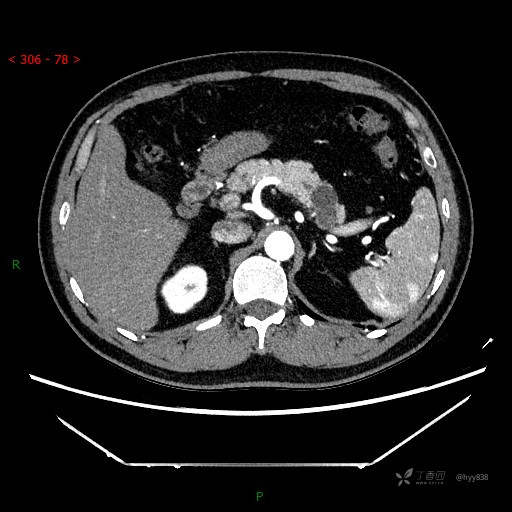

静脉期